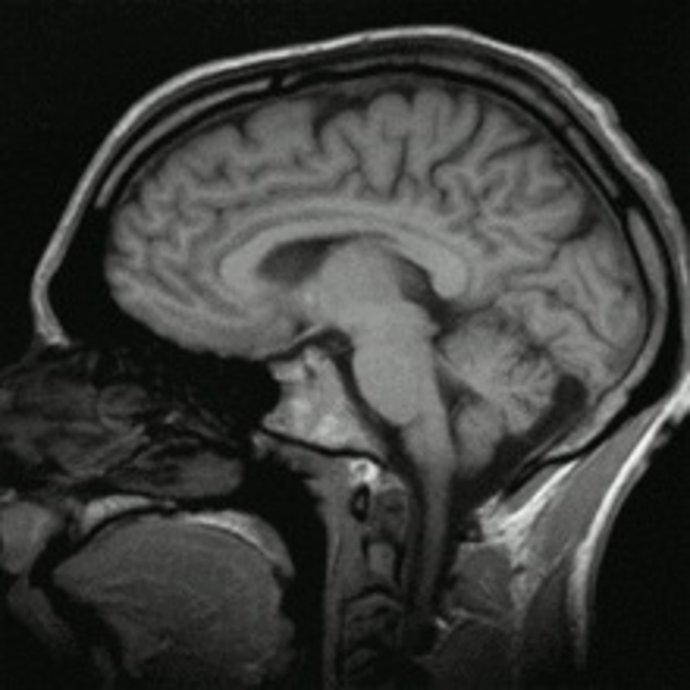

cerebro

WIKIMEDIA COMMONS

Para el estudio, los investigadores del Hospital McLean, en Massachusetts y un equipo de la Universidad de Utah emplearon imágenes por resonancia magnética (IRM) preparadas para detectar patrones microscópicos en las conexiones cerebrales. La prueba detectó en un 94 por ciento de los casos una forma de autismo.

El equipo realizó controles de este tipo en los cerebros de 30 personas con autismo y otras 30 personas sin la condición. Así, hallaron que el circuito cerebral es muy diferente en quienes padecen autismo, comparado con las personas con un funcionamiento cerebral normal, especialmente en zonas del cerebro relacionadas con el lenguaje y la función social y emocional.

A través del análisis de seis aspectos del circuito cerebral, el test pudo detectar correctamente a las personas diagnosticadas con autismo con un 94 por ciento de exactitud. Un nuevo estudio con dos grupos diferentes de participantes mostró el mismo nivel de alta precisión.